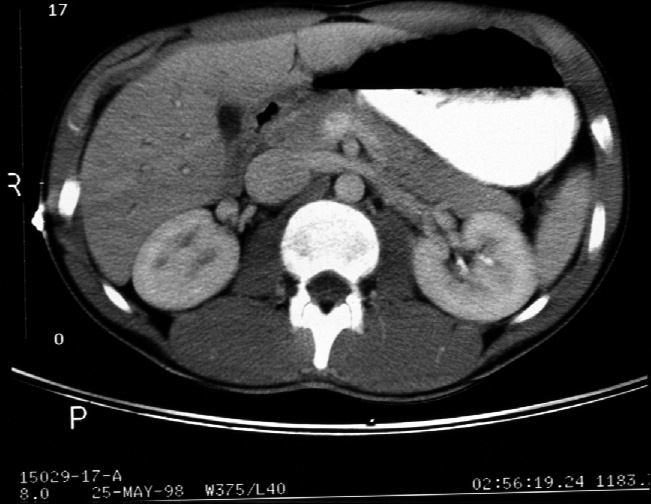

Identify -- stomach, liver, right kidney, left kidney, aorta, inferior

vena cava, pancreas, superior mesenteric artery, superior mesenteric vein,

gall bladder, left renal vein, spleen